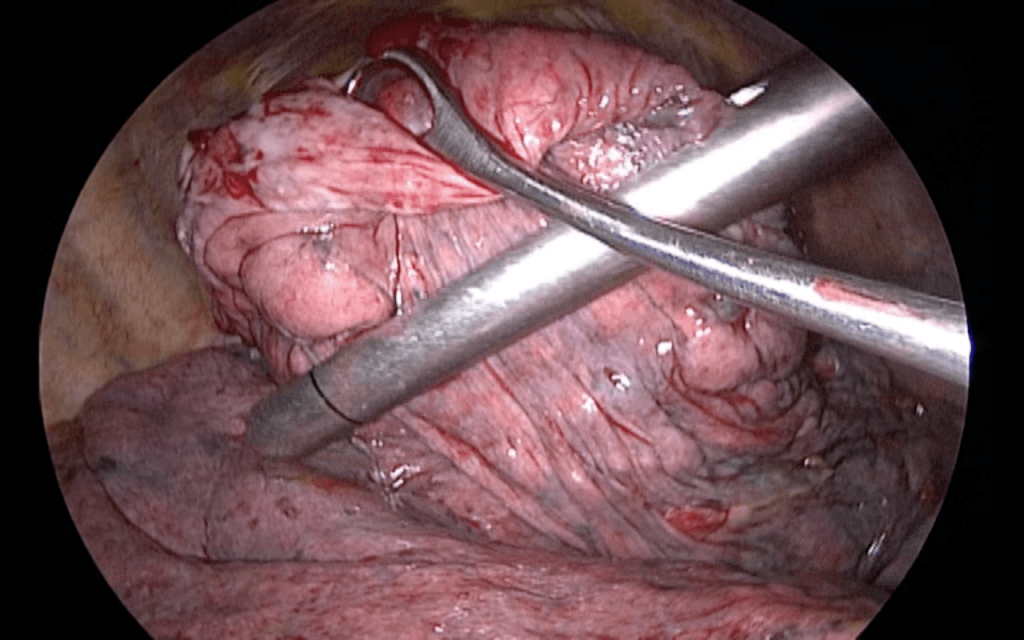

Manejo quirúrgico del EPOC enfisematoso severo

Resección con reducción de volumen pulmonar del EPOC con enfisema heterogéneo.